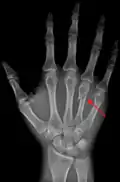

![]() The fourth metacarpal. (Left.) | |

The fourth metacarpal bone (metacarpal bone of the ring finger) is shorter and smaller than the third.

A fractured right hand fourth metacarpal (boxer's fracture).